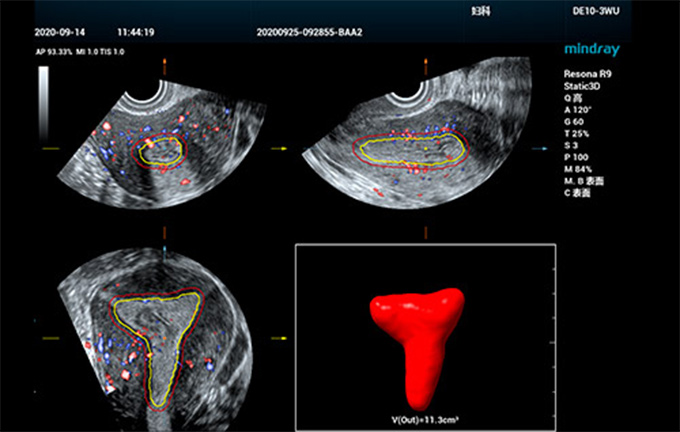

Quantification efficace de l'endomètre

Ces dernières annÊes, les taux d'infertilitÊ fÊminine ont augmentÊ, et les femmes sont exposÊes à un risque accru de maladies et de tumeurs de l'appareil reproducteur liÊes à des modifications des habitudes de vie, à la pollution environnementale et à des troubles physiques. Le r?le de l'Êchographie dans l'examen gynÊcologique est irrempla?able, notamment dans les scÊnarios avant la conception. Cependant, les examens d'Êchographie classiques sont fastidieux et chronophages, reposant en grande partie sur un ajustement manuel.

Smart ERA

Afin d'amÊliorer l'efficacitÊ et l'exactitude du diagnostic gynÊcologique par Êchographie, rendant ainsi plus accessible le diagnostic prÊcoce des troubles de la reproduction et des tumeurs, Mindray a dÊveloppÊ une sÊrie de solutions intelligentes pour aider les mÊdecins à poser un diagnostic clinique efficace lors de l'examen folliculaire et utÊrin par Êchographie. RÊpondant aux besoins d'examen de la rÊceptivitÊ endomÊtriale, nous avons dÊveloppÊ Smart ERA, le premier outil d'analyse de la rÊceptivitÊ endomÊtriale entièrement automatisÊ du secteur, qui permet une imagerie?3D automatique de l'endomètre, même pour diffÊrents types de structures. L'outil permet de mesurer automatiquement le volume et l'Êpaisseur de l'endomètre ainsi que son indice de flux sanguin. Le fonctionnement rationalisÊ amÊliore considÊrablement la cohÊrence de l'examen et l'efficacitÊ du diagnostic, ce qui permet aux Êchographistes de procÊder à l'Êvaluation avant la grossesse avec plus de confiance et de facilitÊ.